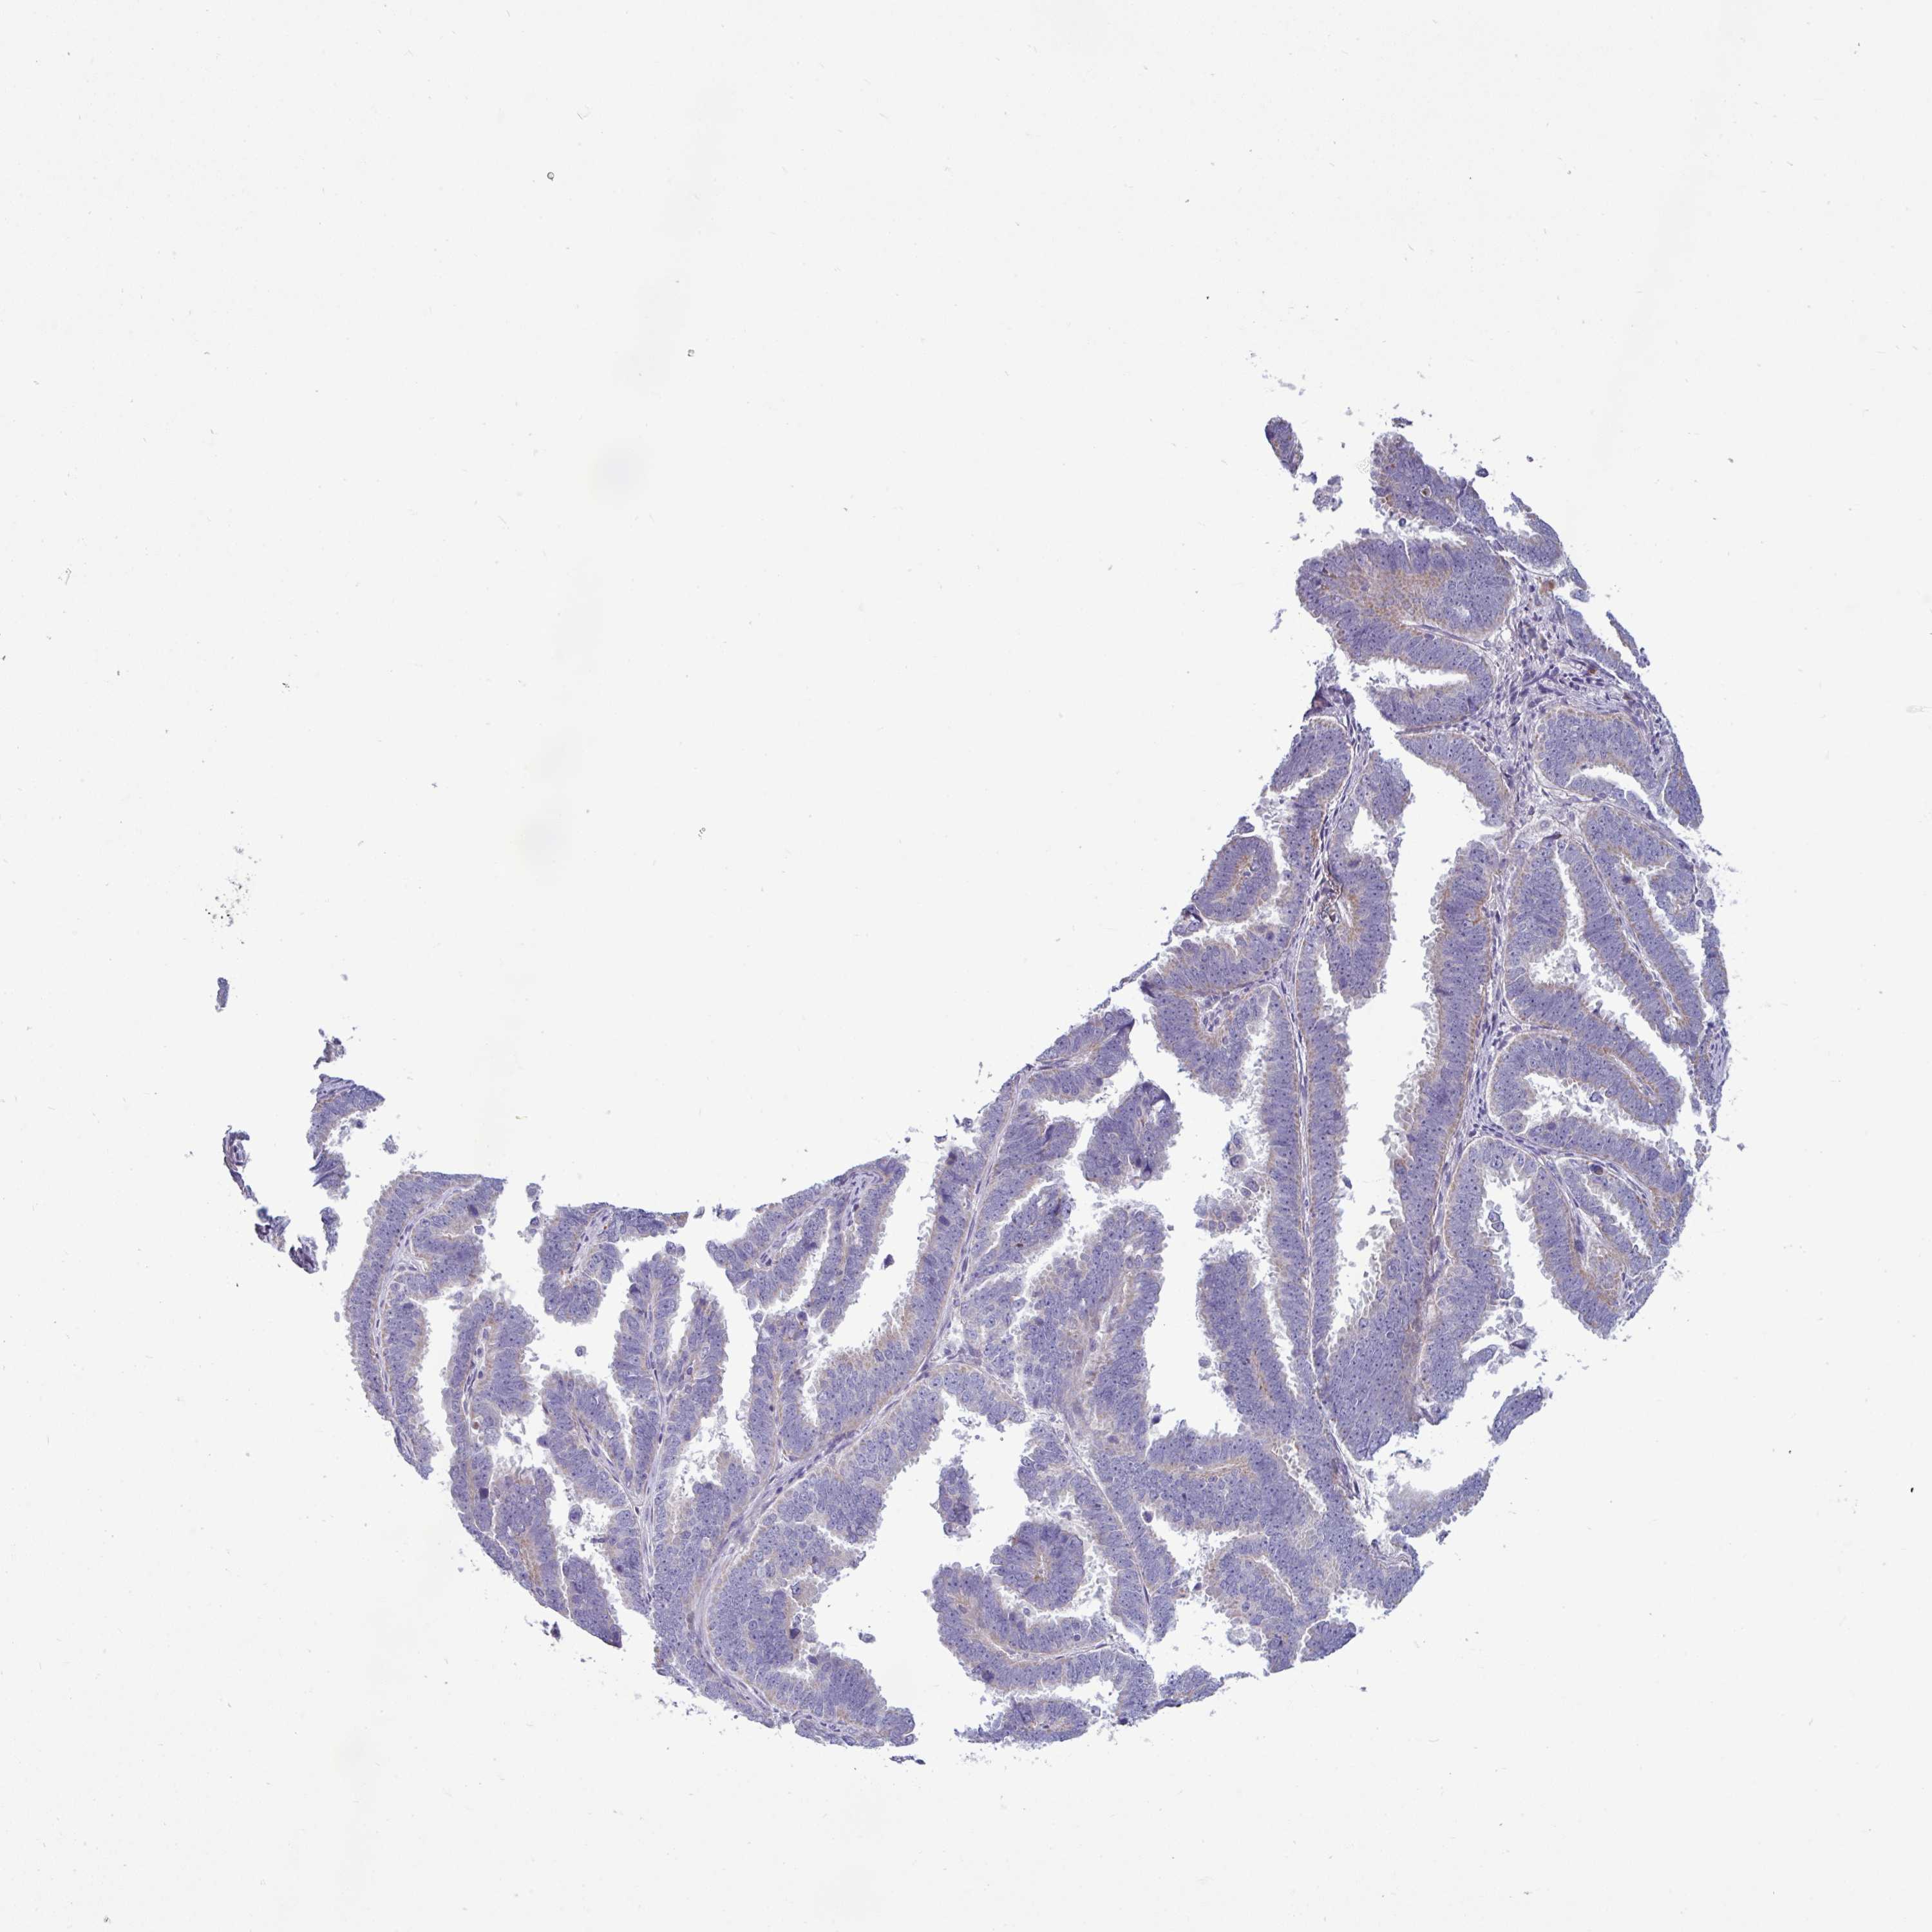

ENDOMETRIAL CANCER - Protein expressioni

A mouse-over function shows sample information and annotation data. Click on an image to view it in a full screen mode. Samples can be filtered based on level of antibody staining by selecting one or several of the following categories: high, medium, low and not detected. The assay and annotation is described here.

Note that samples used for immunohistochemistry by the Human Protein Atlas do not correspond to samples in the TCGA dataset.

Antibody stainingi

Antibody staining in the annotated cell types in the current human tissue is reported as not detected, low, medium, or high, based on conventional immunohistochemistry profiling in selected tissues. This score is based on the combination of the staining intensity and fraction of stained cells.

Each image is clickable and will lead to virtual microscopy that enables deeper exploration of all samples and also displays staining intensity scores, fraction scores and subcellular localization as well as patient and tissue information for each sample.

Antibody HPA049317

Staining

High

Medium

Low

Not detected

Intensity

Strong

Moderate

Weak

Negative

Quantity

>75%

75%-25%

<25%

None

Location

Nuclear

Cytoplasmic/membranous

Cytoplasmic/membranous,nuclear

Adenocarcinoma, NOS